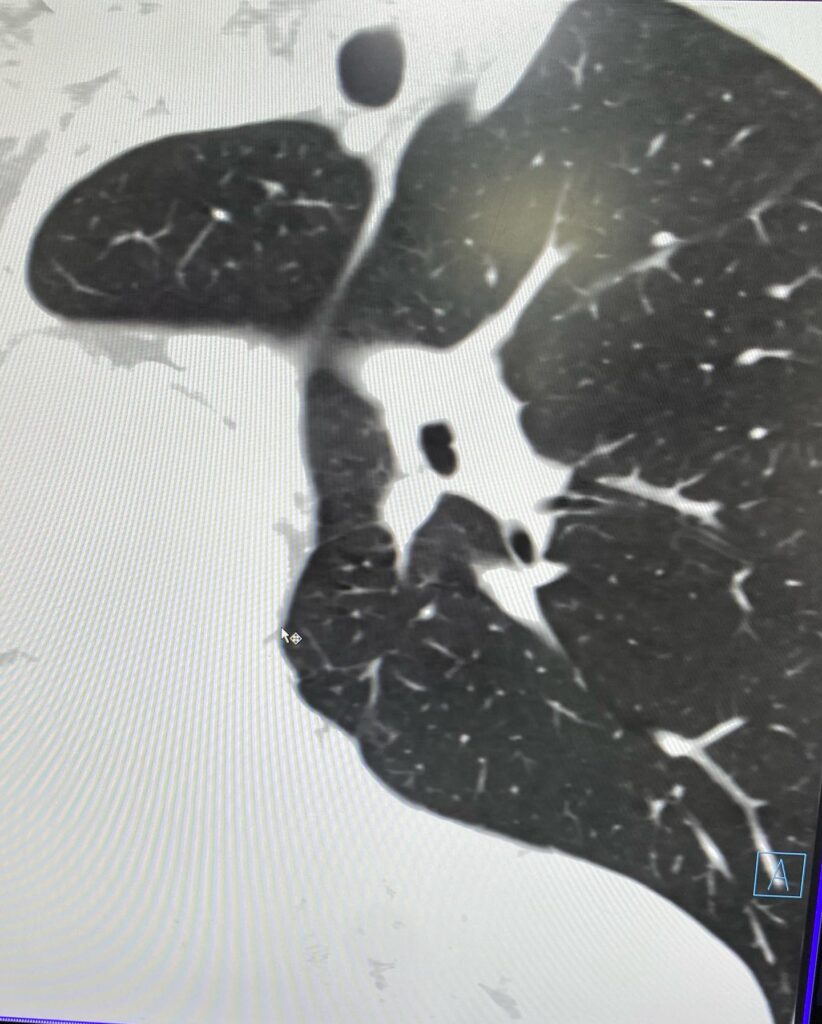

Արդյունքը տպավորիչ էր։ Երեխայի մոտ առկա էր աջ թոքի ագենեզիա (թոքը չի զարգացել, համապատասխանաբար բացակայում էին նաև աջ գլխավոր բրոնխը, աջ թոքային զարկերակը և աջ թոքային երակները), ինչի հետևանքով միջնորմը (այդ թվում սիրտը) տեղակայված է կրծքավանդակի աջ կեսում։

Սրտի նման տեղակայումը հեմոդինամիկ շեղումներ չի առաջացրել. երեխան ունի կառուցվածքային առողջ սիրտ։